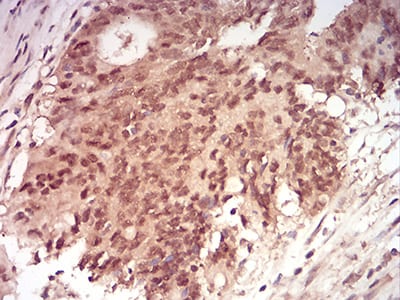

Immunohistochemical analysis of paraffin-embedded human esophageal cancer tissues using RAN mouse mAb with DAB staining.

Immunohistochemical analysis of paraffin-embedded human rectum cancer tissues using RAN mouse mAb with DAB staining.